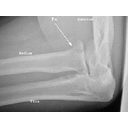

proximal ulnar fracture.jpg